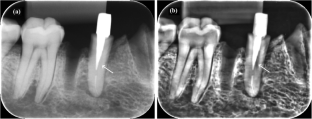

Fig. 1